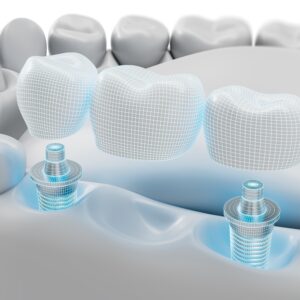

둔산동네비게이션임플란트, 처음이면 알아두어야 할 점은? 안녕하세요. 둔산동네비게이션임플란트 365디지털치과입니다. 치아를 상실한 뒤 임플란트를 고민하게 되는 순간은 대부분 갑작스럽게 찾아옵니다. 갑자기 식사가 불편해지거나, 한쪽으로만 씹게 되는 습관이 생기거나, 시간이 지나면서 주변 치아까지 흔들리는 느낌이 들기도 하는데요. 특히 처음 치료를 고려하는 경우라면 어떤 방식이 나에게 맞는지, 무엇을 기준으로 살펴봐야 하는지 더보기…